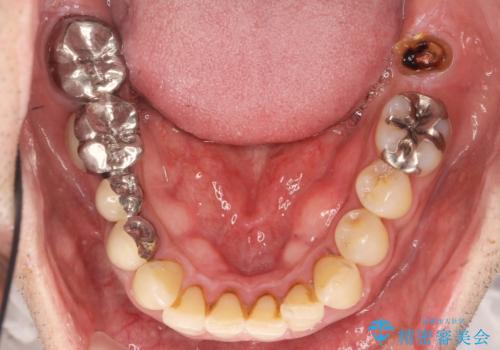

インプラント治療・セラミック治療を含む 全顎的虫歯治療

- 「 仕事が忙しく、虫歯を放置しすぎてしまった。この際全てきっちりと治したい。」と来院されました。

・歯の欠損

・虫歯

・深い虫歯

・欠損の放置による対合歯の挺出

・咬合平面の乱れ

・感染根管

以上のような問題を、徹底的な虫歯治療、歯周外科、インプラント治療、部分矯正治療、精密根管治療を用いてひとつずつ解決ししっかりと長期的に食事を楽しめるような口腔内環境の再構築を目指します。